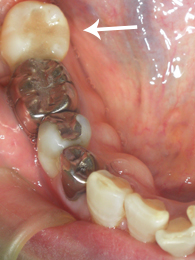

60代 女性 右下7 上牧町在住

〔術前〕